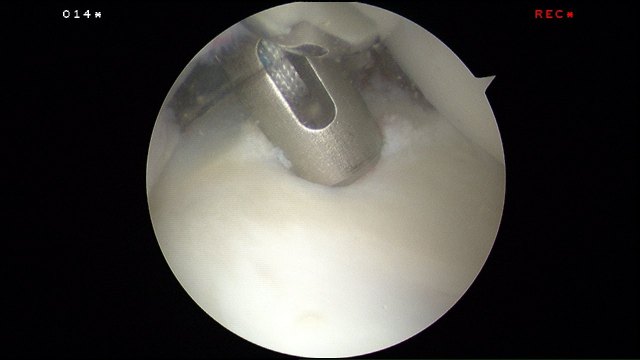

A pilot hole is drilled for the passage of the suture anchor. This drill is inserted through the posterior shoulder portal with the camera in the antero-superior portal.

The 2.9mm bioabsorbable suture anchor is inserted. I like to use a double loaded suture anchor.